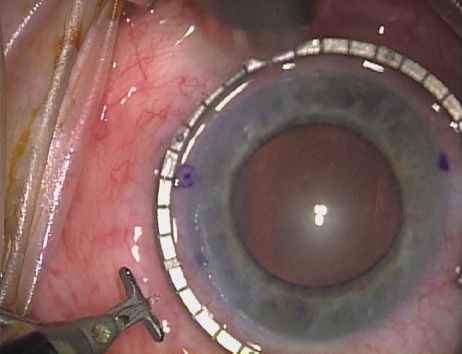

Case 1 is a 68-year-old male who presented for right cataract surgery. His refraction was −1.00 +2.25 × 80 and was recorded as reliable, consistent with his modest cataract density. Keratometry readings were 44.75 × 75 and 43.00 × 165. Corneal topography confirmed slightly more than 2.00 D of regular and slightly oblique cylinder. Consulting the nomogram, a plan was devised for a pair of LRIs to be centered over the 75-degree axis, with each incision delineating 45 degrees of arc. A single plane phaco incision was used and maintained at a size of less than 3.2 mm (Figs. 811).

Fig. 8. Steep meridian is confirmed intraoperatively by keratoscopy. In this left eye viewed from the temporal side, the “short axis” of the corneal mire is seen to be at the 75-degree meridian. (Reprinted from Hardten DR, Lindstrom RL, Davis EA. Phakic Intraocular Lenses: Principles and Practice. Thorofare, NJ: SLACK Incorporated, 2004, with permission.)

Fig. 9. The broad hash marks of the fixation ring/gauge are centered over the 75-degree meridian, using the 6:00 limbal mark for orientation. Alternatively, a Mendez gauge may be used. (Reprinted from Hardten DR, Lindstrom RL, Davis EA. Phakic Intraocular Lenses: Principles and Practice. Thorofare, NJ: SLACK Incorporated, 2004, with permission.)

Fig. 10. The single footplate diamond blade is inserted perpendicular to the corneal surface and at the peripheral most extent of clear corneal tissue. In this case, the nomogram calls for arcuate incisions of 45 degrees. Therefore, the incision is begun approximately 22.5 degrees to one side of the broad hash mark. (Reprinted from Hardten DR, Lindstrom RL, Davis EA. Phakic Intraocular Lenses: Principles and Practice. Thorofare, NJ: SLACK Incorporated, 2004, with permission.)

Fig. 11. Opposite relaxing incision is completed. (Reprinted from Hardten DR, Lindstrom RL, Davis EA. Phakic Intraocular Lenses: Principles and Practice. Thorofare, NJ: SLACK Incorporated, 2004, with permission.)